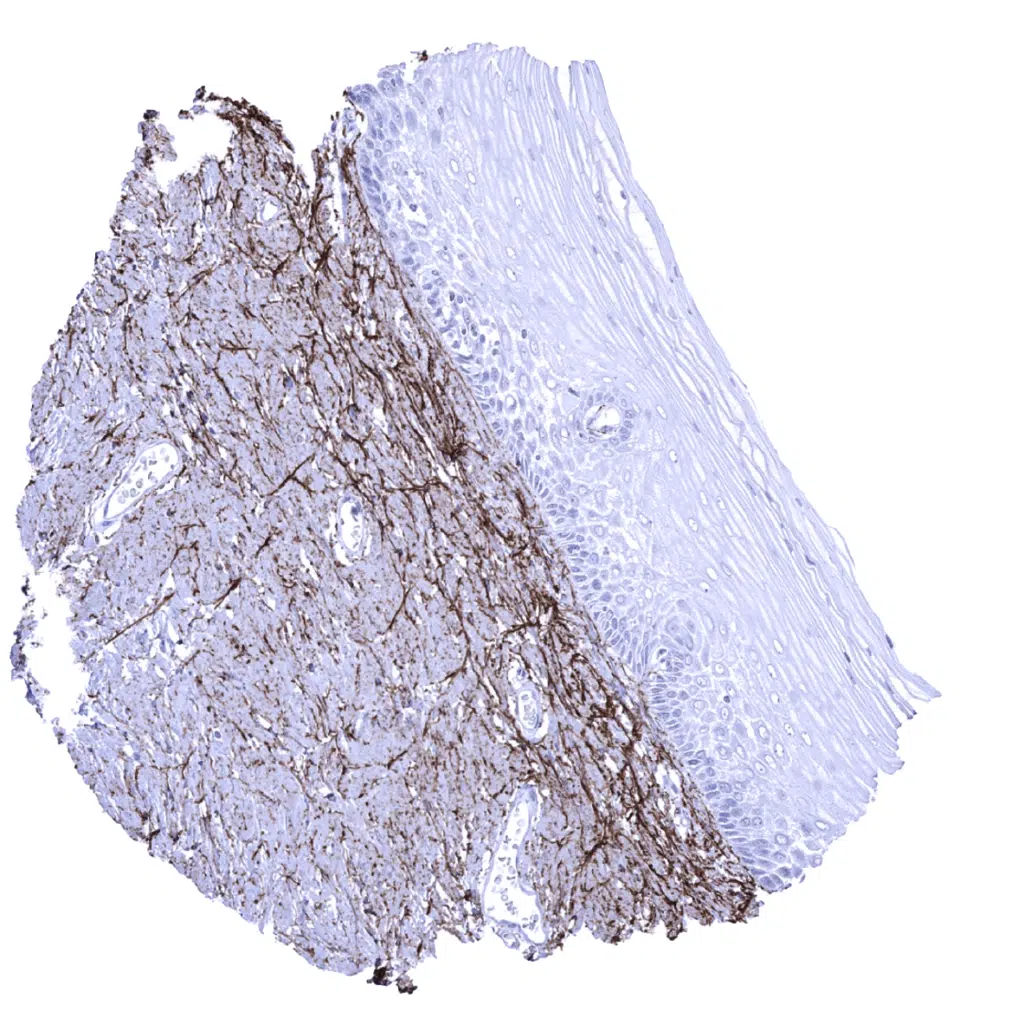

Uterus, ectocervix: Elastin fibres abundantly occur below the squamous epithelium.